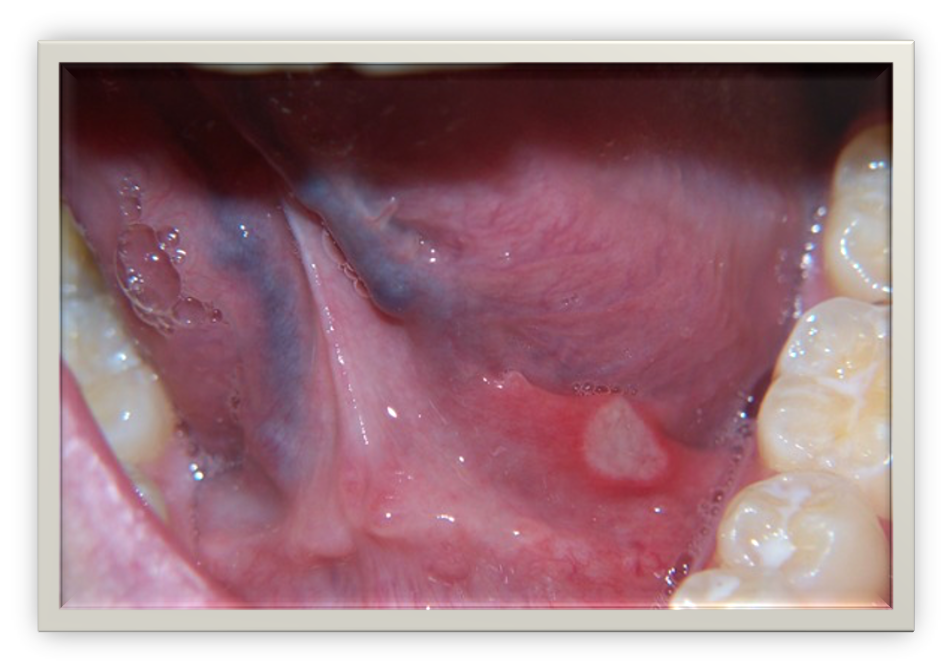

Also known as hereditary intestinal polyposis, Peutz Jeger's Syndrome is a hereditary condition characterized by the development of intestinal polyps. Prevalence in the US ranges from 1 in 50,000 to 1 in 200,000.11,22 The polyps associated with PJS are histologically distinct, typically begin developing in childhood and are most common in the small bowel and colon. The GI polyps may cause GI bleeding, anemia and abdominal pain due to intussusception, obstruction or infaction.22PJS is known to produce perioral and intraoral pigmentations as well as pigmented areas on the hands and feet (Figure 8).11,23 Oral melanotic macules are common and may be the first clinical sign of the disease, placing dental professionals on the front line of diagnosis of this condition. Diagnosis is based on family history, detection of polyps through endoscopy and/or colonoscopy, and mucocutaneous pigmentation.

Fig 9. Peutz Jegher’s syndrome

oral pigmentation.

Figure 9